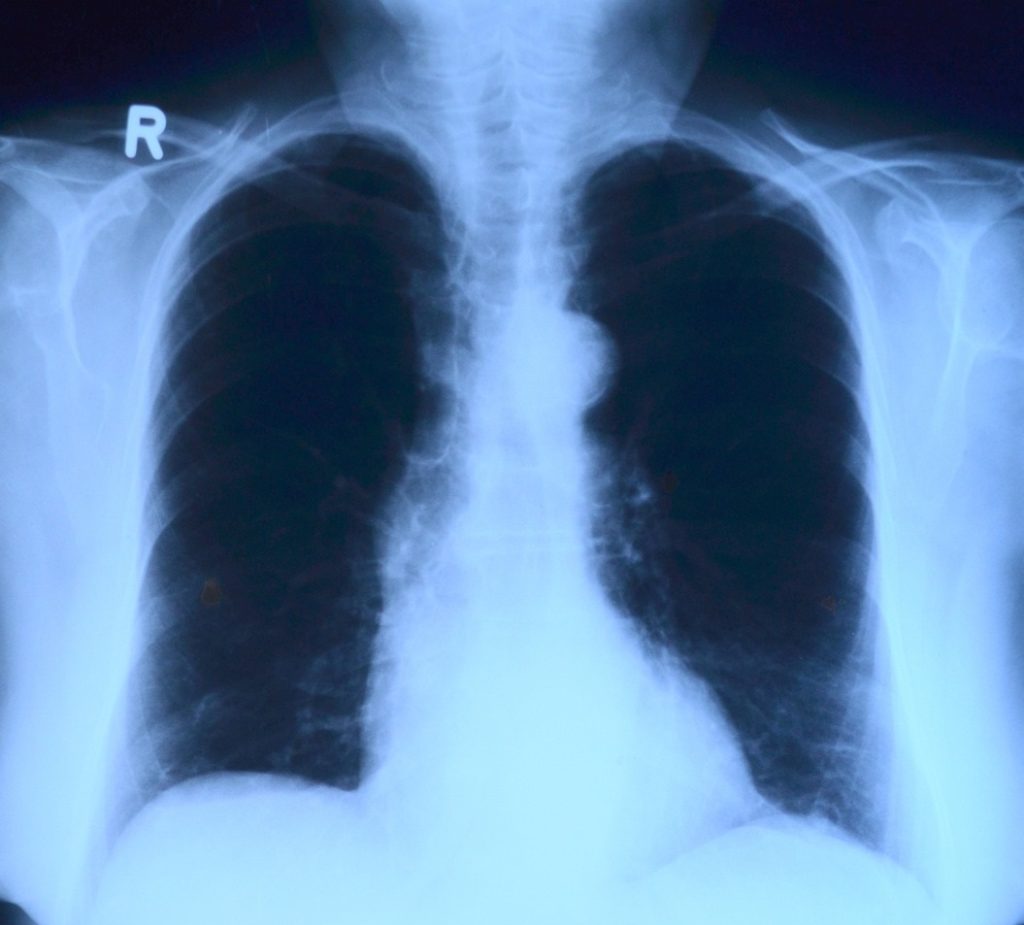

Sve više oboljelih od atipične upale pluća

Raste broj slučajeva upale pluća tijekom ljeta, a pogotovo onih s atipičnom upalom koju uzrokuje bakterije mikoplazma.

Atipične upale pluća imaju postupni nastanak uz izostanak tipične kliničke slike te su uzrokovane patogenim mikroorganizmima koji se rijetko rutinski identificiraju u kliničkoj praksi.